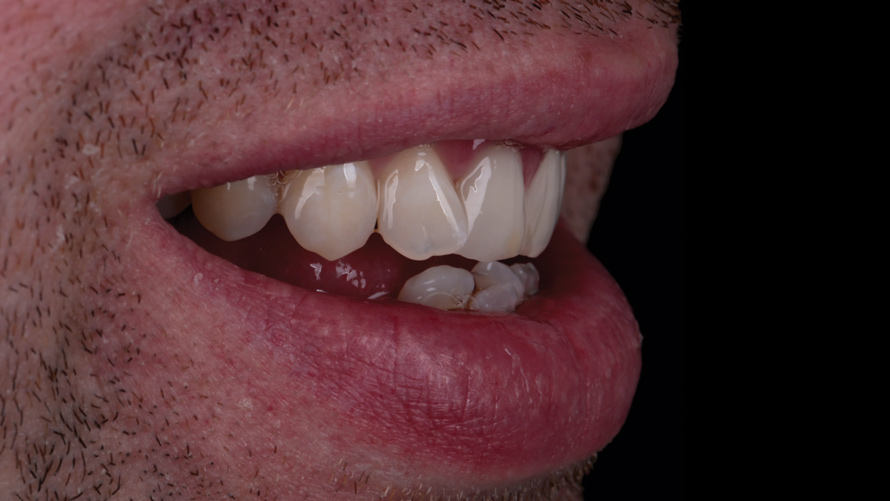

Eight weeks after the initial start of the walking bleach procedure, the final layered lithium disilicate crown was tried-in and evaluated for function and esthetics. Upon patient approval, the intaglio surface of the crown was etched for 20 seconds with a 9.6% hydrofluoric acid etchant, rinsed, and then scrubbed with a 37.5% orthophosphoric acid solution to clean out any ceramic debris. The crown was then placed into an ultrasonic bath of 91% isopropyl alcohol for 5 minutes, after which the intaglio surface was coated with silane and placed under a warm air dryer for 1 minute. A translucent self-adhesive resin cement was used to bond the final restoration to the preparation. The patients both stated that they approved of the form, function, and esthetics of the definitive restoration and that they were very pleased with the final results (Figure 13 through Figure 18). Routine periodic evaluations and radiographs were scheduled to monitor their oral health and esthetics.

(16.) Case 2: Retracted full-smile view of the definitive all-ceramic restoration on the maxillary left central incisor.

Figure 16